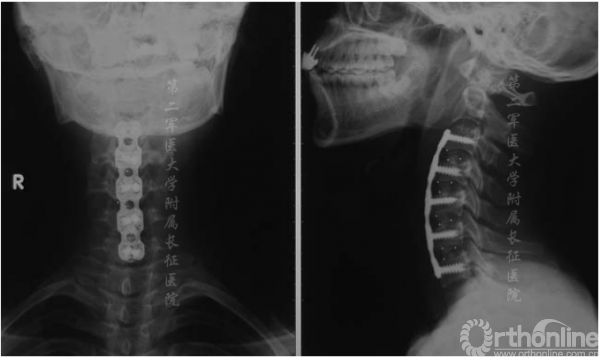

图3.术后x线片显示颈椎前路椎间盘切除术及融合内固定术

颈椎中立位MRI可见颈椎后凸在C4-C5或C5-C6处具有顶点(图1),且脊髓出现轻度萎缩。屈颈位MRI可见硬膜外高信号影及硬膜囊后壁前移(图2)。头颅MRI未显示异常。根据MRI将患者诊断为平山病伴颈椎后凸畸形。入院三天后,患者在全麻下接受颈前路椎间盘切除术并在C3-C7水平融合以重建颈椎序列和脊柱前凸(图3)。